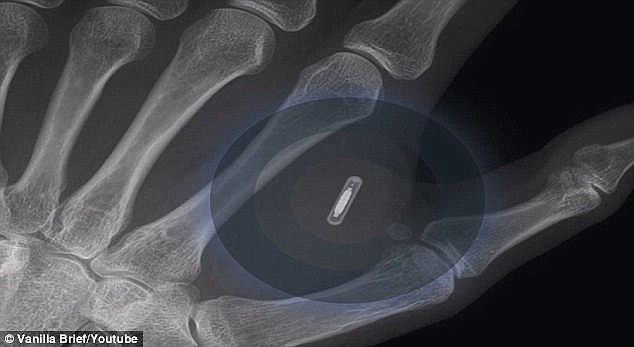

World Economic Forum Suggests There Are 'Solid, Rational' Reasons For Children to Be Microchipped

Not doing their Bond villain reputation status any favors, the World Economic Forum published an article suggesting it would be a “solid, rational” move for children to be implanted with microchips.

The idea is promoted in a blog post on the Davos elite’s website which discusses the future of augmented reality and an “augmented society.”

WEF Announces Plan to Track Children like Dogs with RFID Tags

The World Economic Forum has outlined their plans for all children across the globe to be implanted with trackable RFID chips as part of ‘The Great Reset’ agenda.

Radio-frequency identification (RFID) tags put out a “pulse” that can be read by an electronic reader.